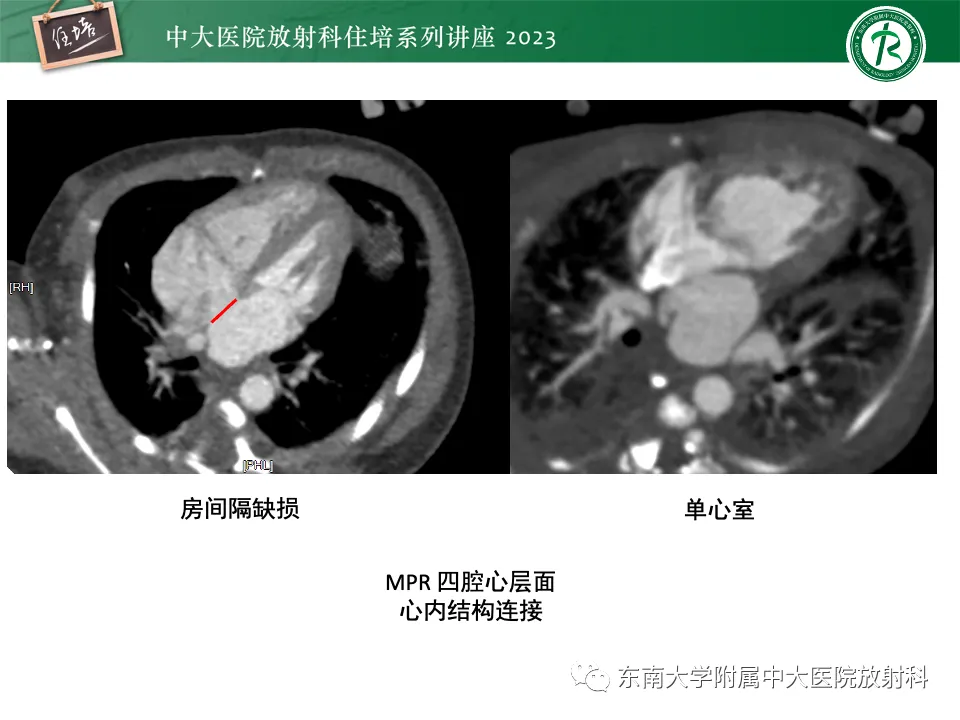

>精美课件丨心脏大血管常见疾病CT图像后处理要点

精美课件丨心脏大血管常见疾病CT图像后处理要点

来源:东南大学附属中大医院医学影像科